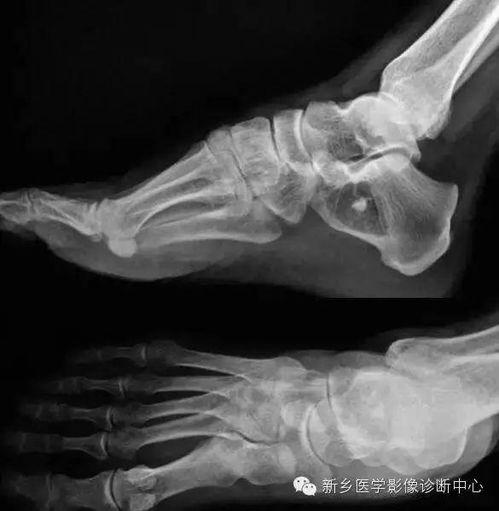

在医学领域,骨骼照片同样发挥着重要作用。比如,这张骨折患者的骨骼照片,医生可以通过它来判断骨折的程度和位置,从而制定出最佳的治疗方案。此外,骨骼照片还可以用于研究骨骼疾病,如骨质疏松症等。